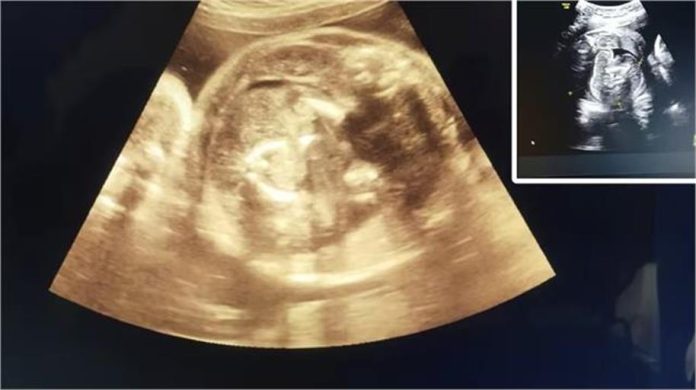

महाराष्ट्र के बुलढाना जिले के एक सरकारी अस्पताल में एक दुर्लभ चिकित्सा मामला सामने आया, जिसने डॉक्टरों को भी हैरान कर दिया। जिले के मोताला तहसील से आई 32 वर्षीय गर्भवती महिला की सोनोग्राफी के दौरान डॉक्टरों ने पाया कि उसके गर्भ में पल रहे बच्चे के पेट में भी एक भ्रूण मौजूद है।

इस स्थिति को चिकित्सा जगत में Fetus in Feto कहा जाता है, जो बेहद दुर्लभ मामला है। सिविल सर्जन डॉ. भागवत भुसारी के अनुसार, दुनियाभर में अब तक ऐसे लगभग 200 मामले सामने आ चुके हैं, जिनमें से भारत में केवल 15 से 20 ही दर्ज हुए हैं। विशेषज्ञों का कहना है कि मां को कोई खतरा नहीं होगा, लेकिन नवजात के लिए जल्द से जल्द उपचार आवश्यक होगा ताकि उसकी सामान्य वृद्धि प्रभावित न हो।